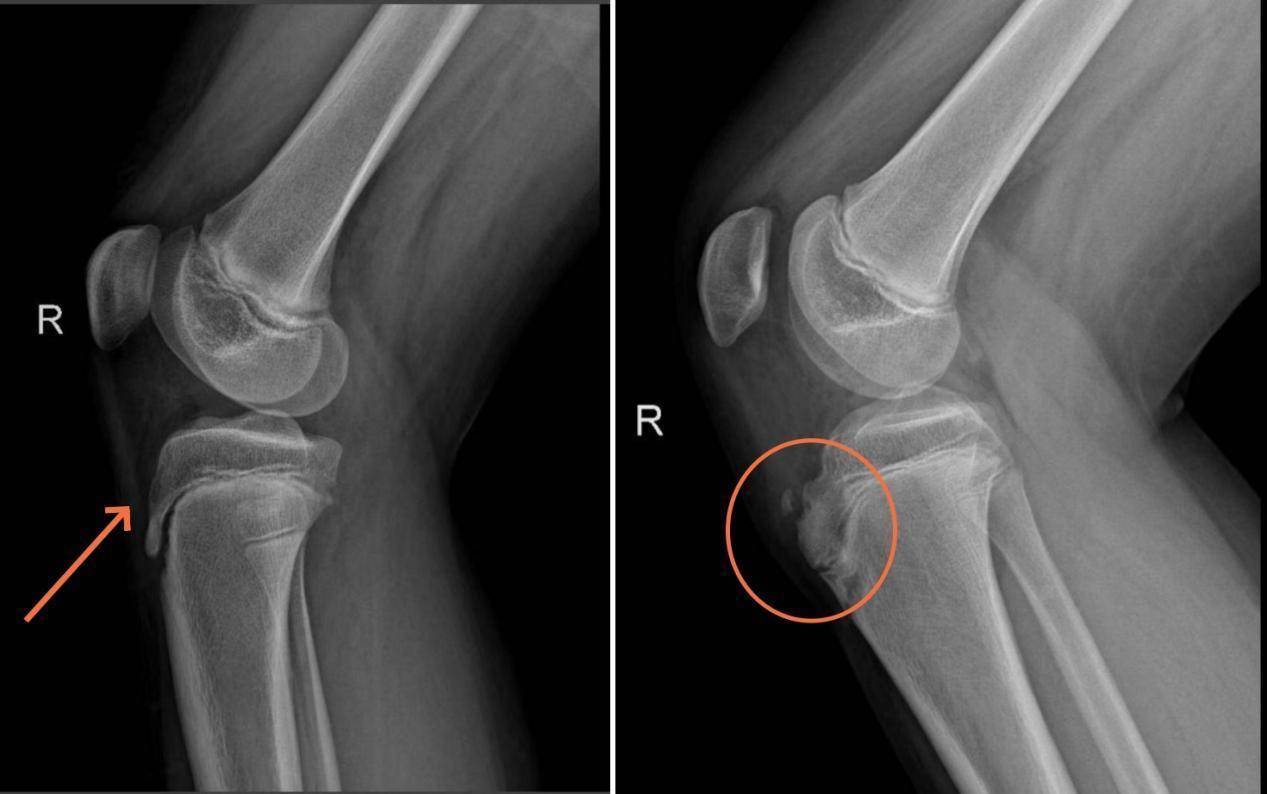

李宝军主任医师稽查了男孩的膝要津以后,会诊为“右侧胫骨结节骨软骨炎”,完善右膝要津正侧位X线,X线的终局会诊合适“右胫骨结节骨软骨炎”。

左图为时常的青少年胫骨结节,右图为病变的青少年胫骨结节,可见显明了得